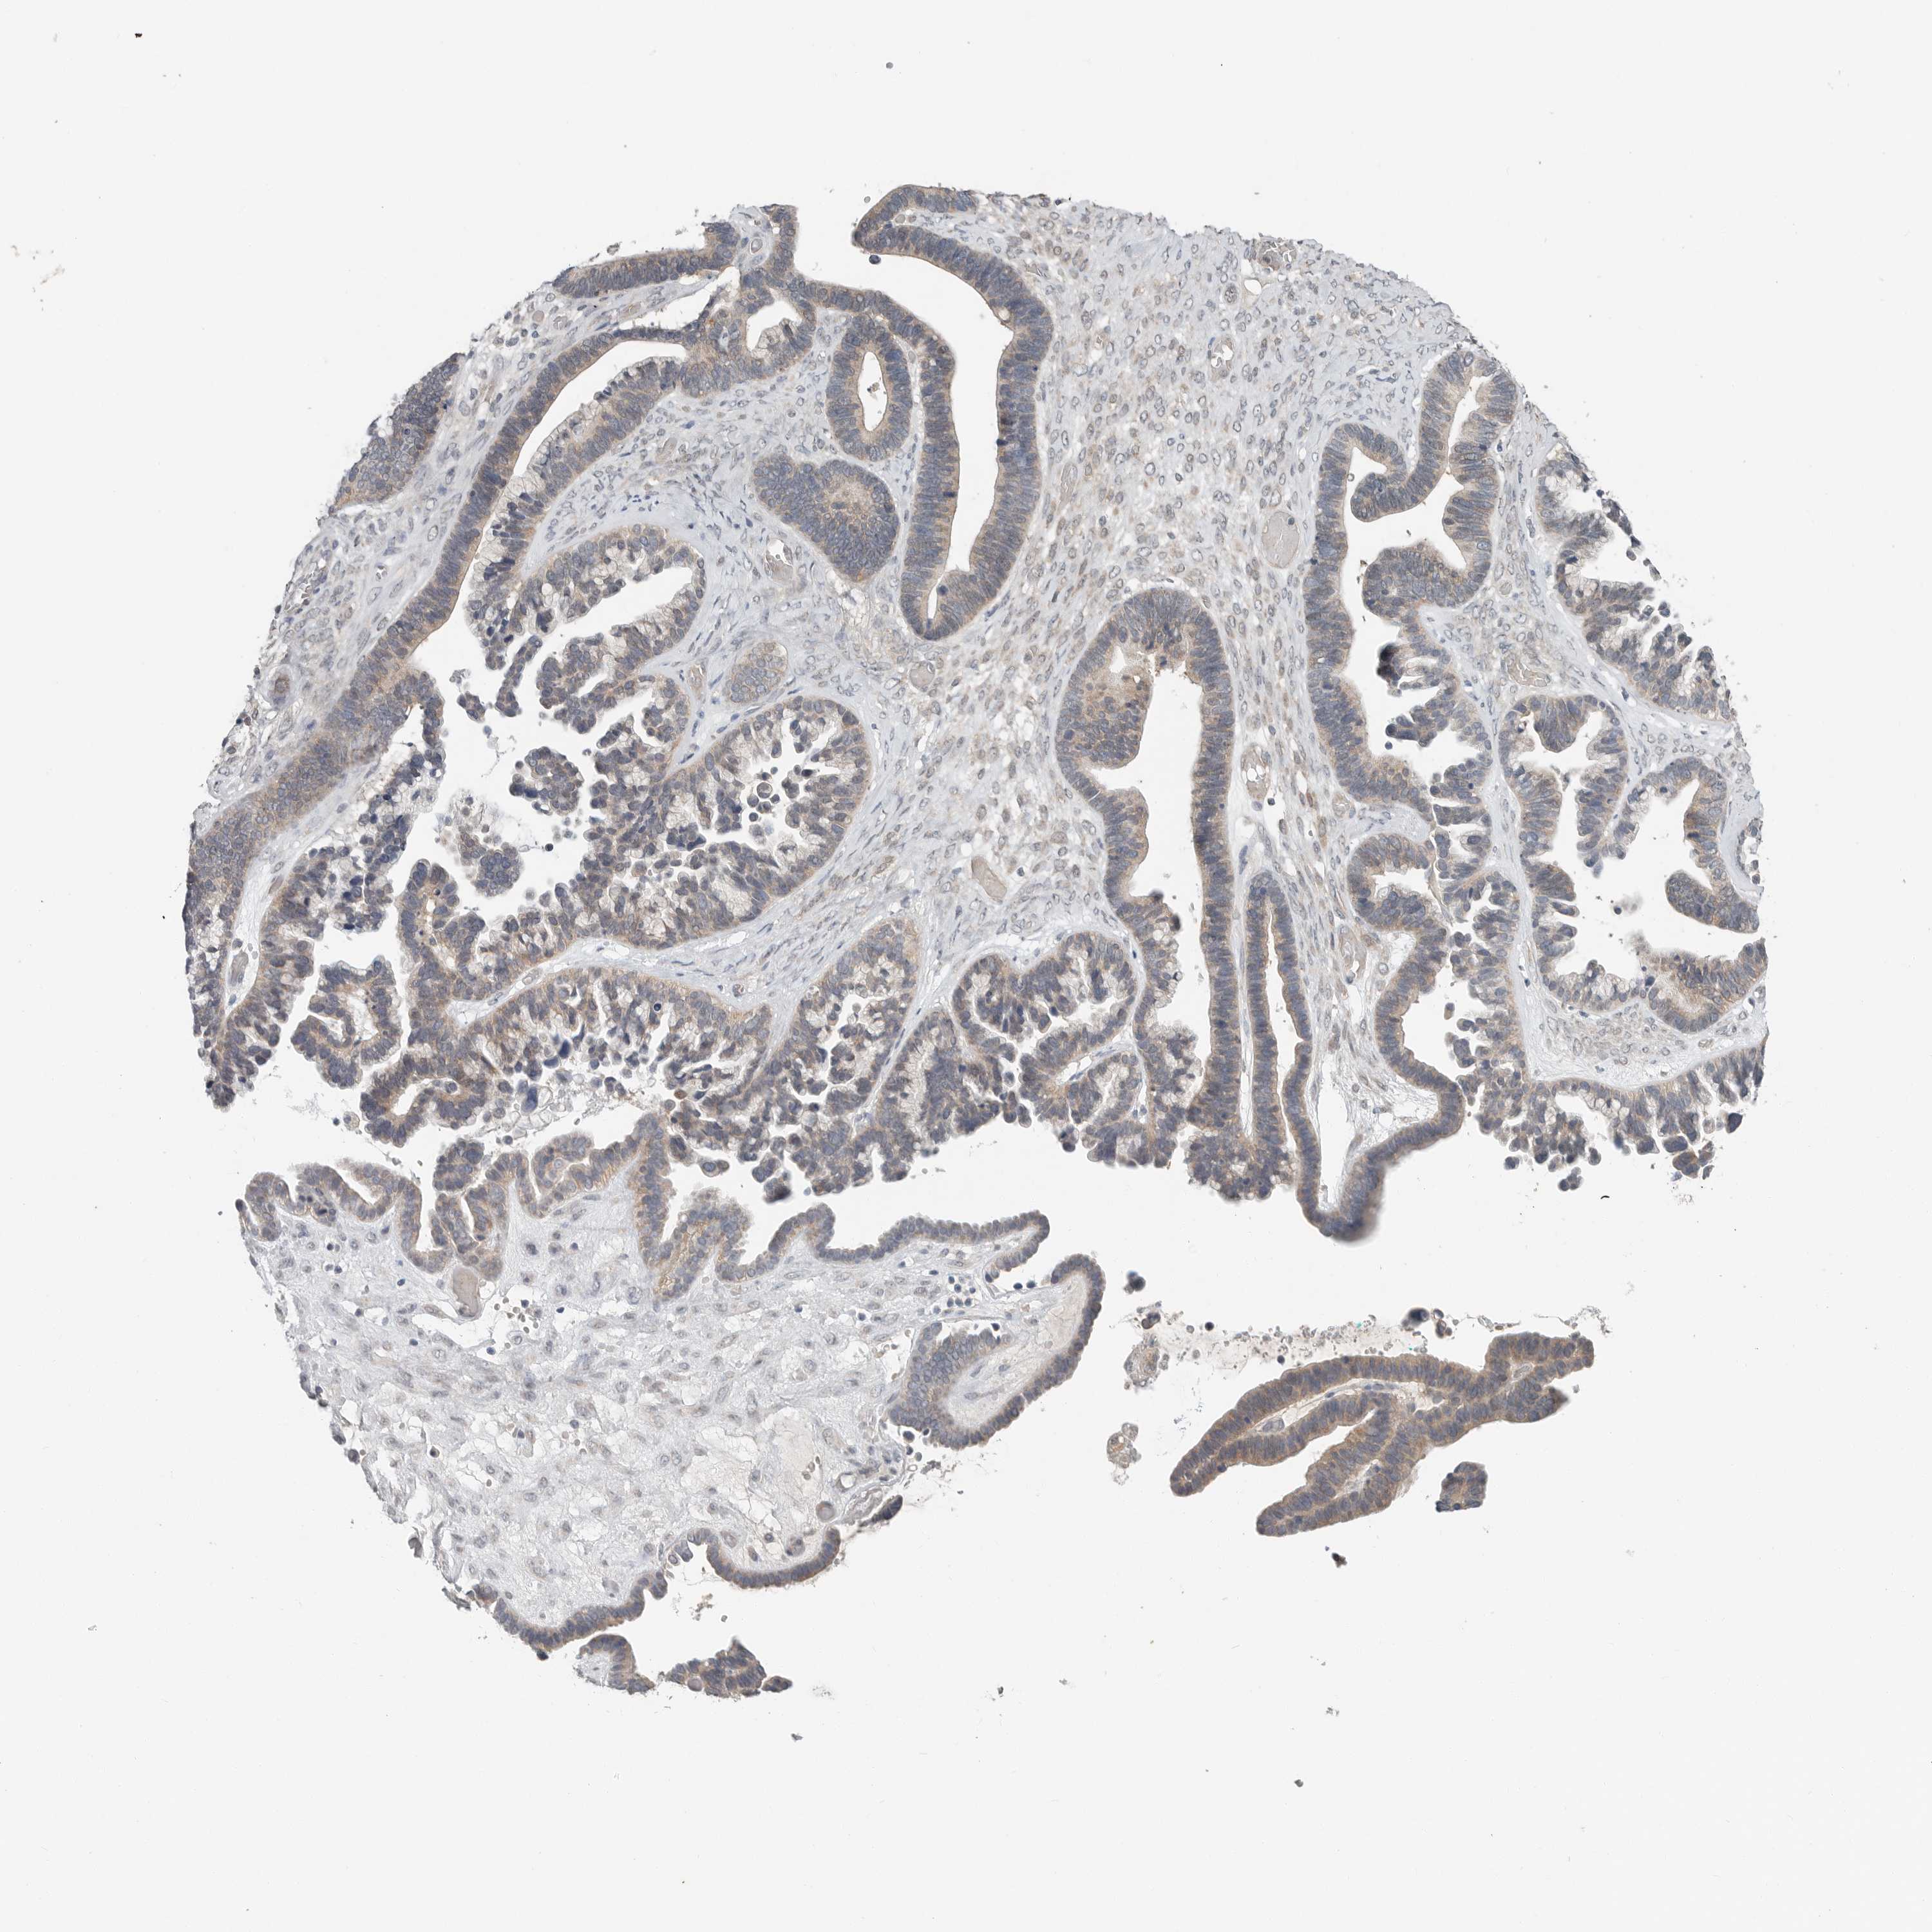

OVARIAN CANCER - Protein expressioni

A mouse-over function shows sample information and annotation data. Click on an image to view it in a full screen mode. Samples can be filtered based on level of antibody staining by selecting one or several of the following categories: high, medium, low and not detected. The assay and annotation is described here.

Note that samples used for immunohistochemistry by the Human Protein Atlas do not correspond to samples in the TCGA dataset.

Antibody stainingi

Antibody staining in the annotated cell types in the current human tissue is reported as not detected, low, medium, or high, based on conventional immunohistochemistry profiling in selected tissues. This score is based on the combination of the staining intensity and fraction of stained cells.

Each image is clickable and will lead to virtual microscopy that enables deeper exploration of all samples and also displays staining intensity scores, fraction scores and subcellular localization as well as patient and tissue information for each sample.

Antibody CAB026139

Staining

High

Medium

Low

Not detected

Intensity

Strong

Moderate

Weak

Negative

Quantity

>75%

75%-25%

<25%

None

Location

Nuclear

Cytoplasmic/membranous

Cytoplasmic/membranous,nuclear

Cystadenocarcinoma, serous, NOS

Carcinoma, endometroid

Cystadenocarcinoma, mucinous, NOS

Carcinoma, NOS